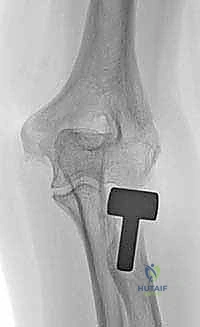

5. تركيب الغرسة المعيارية (Modular Implantation)

يتم إدخال "الجذع" (Stem) داخل القناة العظمية للكعبرة، ثم يتم تركيب "الرأس" (Head) المعدني فوقه. الميزة هنا أن النظام "معياري"، أي يمكن تركيب رأس بحجم معين على جذع بحجم مختلف، ليتناسب تماماً مع تشريح المريض.

الغرسات المعيارية (Modular Implants): التكنولوجيا التي غيرت قواعد اللعبة

في الماضي، كانت تستخدم غرسات من قطعة واحدة (Monoblock)، والتي كانت تجعل من الصعب جداً مطابقة تشريح كل مريض. أما اليوم، وفي عيادة الأستاذ الدكتور محمد هطيف، يتم استخدام الغرسات المعيارية الحديثة.

هذه الغرسات تتكون من أجزاء منفصلة (رأس وعنق وجذع) يتم تجميعها داخل غرفة العمليات. تُصنع عادة من سبائك الكوبالت-كروم (Cobalt-Chrome) أو التيتانيوم (Titanium)، وهي مواد خاملة حيوياً وتتميز بصلابة شديدة ونعومة فائقة تمنع احتكاك العظام.